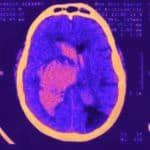

- Hematoma cerebral

- Hemorragia subaracnóide

- AVC maligno

- Drenagem de hematoma